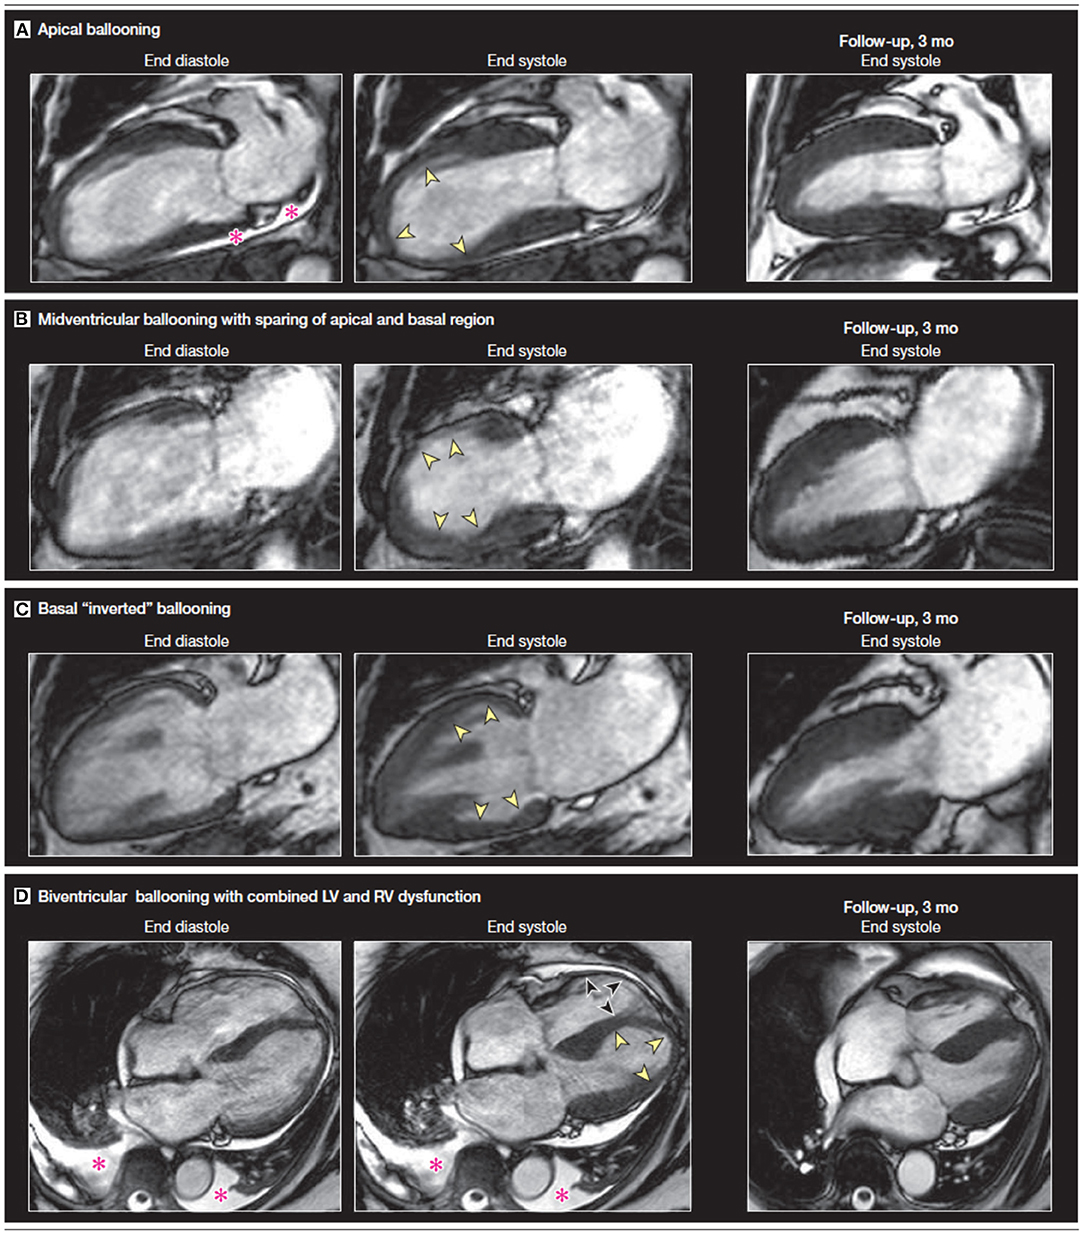

Cine CMR sequences allow for more detailed assessment of LV and RV function, ventricular wall motion abnormalities, and possible complications of stress CM (38, 39). While the “apical ballooning” pattern of wall motion accounts for around 75–80% of patients, stress CM can also present in the form of other less common variants, namely the mid-ventricular variant or the inverted variant which are discussed earlier (40, 41) (Figure 2). The cine sequence can also be used to demonstrate LVOTO with or without systolic anterior motion of the mitral valve leaflet as well as functional mitral regurgitation (39). These complications can be further assessed with phase contrast velocity imaging in order to generate quantitative values such as LV outflow tract gradient.

Figure 2. A comparison of vertical long axis CMR cine sequence images on diagnosis and at 3-month follow-up showing a recovery of wall motion abnormalities. The four sets of images display four different variants associated with stress CM. The pink asterisk denotes a pericardial effusion. Yellow arrows indicate apical akinesis while the black arrows indicate RV apical akinesis in the biventricular ballooning variant. Figure adapted from Figure 2 on Clinical Characteristics and cardiovascular magnetic resonance findings in stress (Takotsubo) cardiomyopathy by Eitel et al. (41).

Additionally, CMR allows for more quantitative assessment of RV function. RV involvement has been assessed by CMR in multiple studies: patients with RV dysfunction were older, had with longer hospital stays, had more frequent preceding stressful events, had significantly more pleural effusions, and had a lower LV EF compared to those that did not have RV involvement (41, 42).